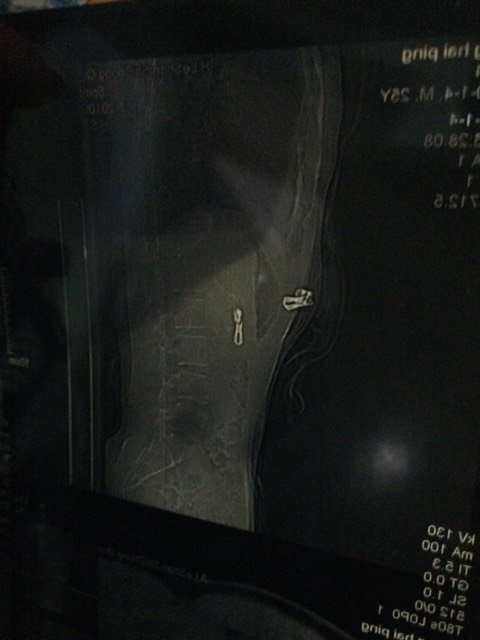

有医生在吗,帮忙看看这个腰有没有问题 会不会引起脚痛啊 有医生在吗,帮忙看看这个腰有没有问题。会不会引起脚痛啊。 点击展开 素颜姑娘不怕雨淋 2015-01-04 18:48 为您推荐: 其他回答 祝宝妈好孕! 👀👀👀👀 2015-01-04 22:43 你好,根据你的图片来看,脊柱的生理弯曲有点变直,没有看到明显的增生。属于腰椎轻度退变吧。脚痛一般是椎间盘突出压迫神经引起的,需要做CT检查,从这上面不好说。 乐乐1abc 2015-01-04 20:49 n要注意休息 Love smile giggle 2015-01-04 19:52 ????? 一月宝 2015-01-04 19:38 问医生吧。 小小双201314 2015-01-04 19:01 加载更多 相关问题 为什么我什么都没有做 腰好痛啊!扯着脚痛 这是什么情况 今天搬了重东西,现在腰好酸痛,请问医生会有问题吗? 请问医生我才刚怀孕五个月左腰就疼得历害有没有什么好办法吗?